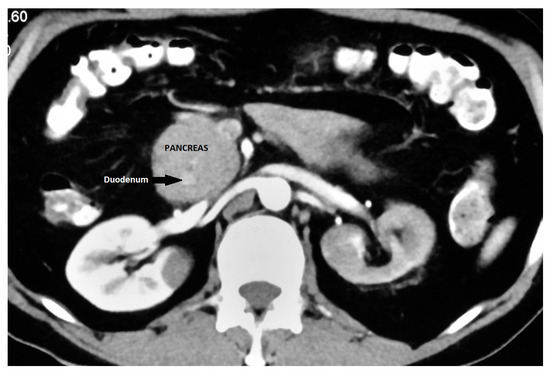

11. EUS in Annular Pancreas